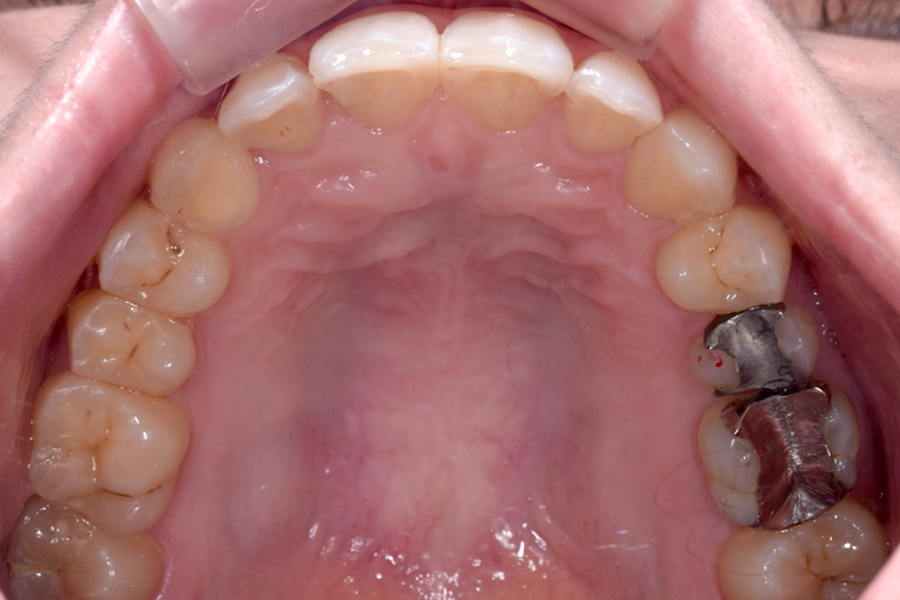

| 主訴 | 見た目を治したい、歯を白くしたい |

|---|---|

| 治療期間 | 1年6か月 |

| 治療費 | マウスピース矯正と ホームホワイトニングセット 1,022,350円(税込) |

| 治療内容 | 目立ちにくいマウスピース矯正 (非抜歯矯正) 歯と歯の間に隙間をつくることにより、歯列弓を広げながら治療を行いました。 また矯正用マウスピースをトレー代わりにし、ジェルを入れてホームホワイトニングを同時に行っております。 |

| 治療のリスク | ・後戻りする可能性があるのでリテーナーを最低でも矯正期間以上はつける必要があります。 ・ホワイトニング後、一時的に痛みが出る場合があります。 |